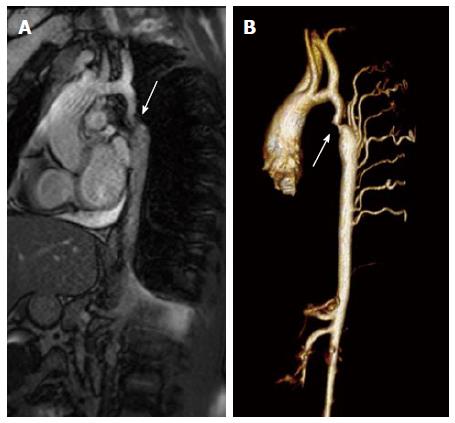

- Cardiovascular MRI/CT

- Recommended for adolescent and adult patients